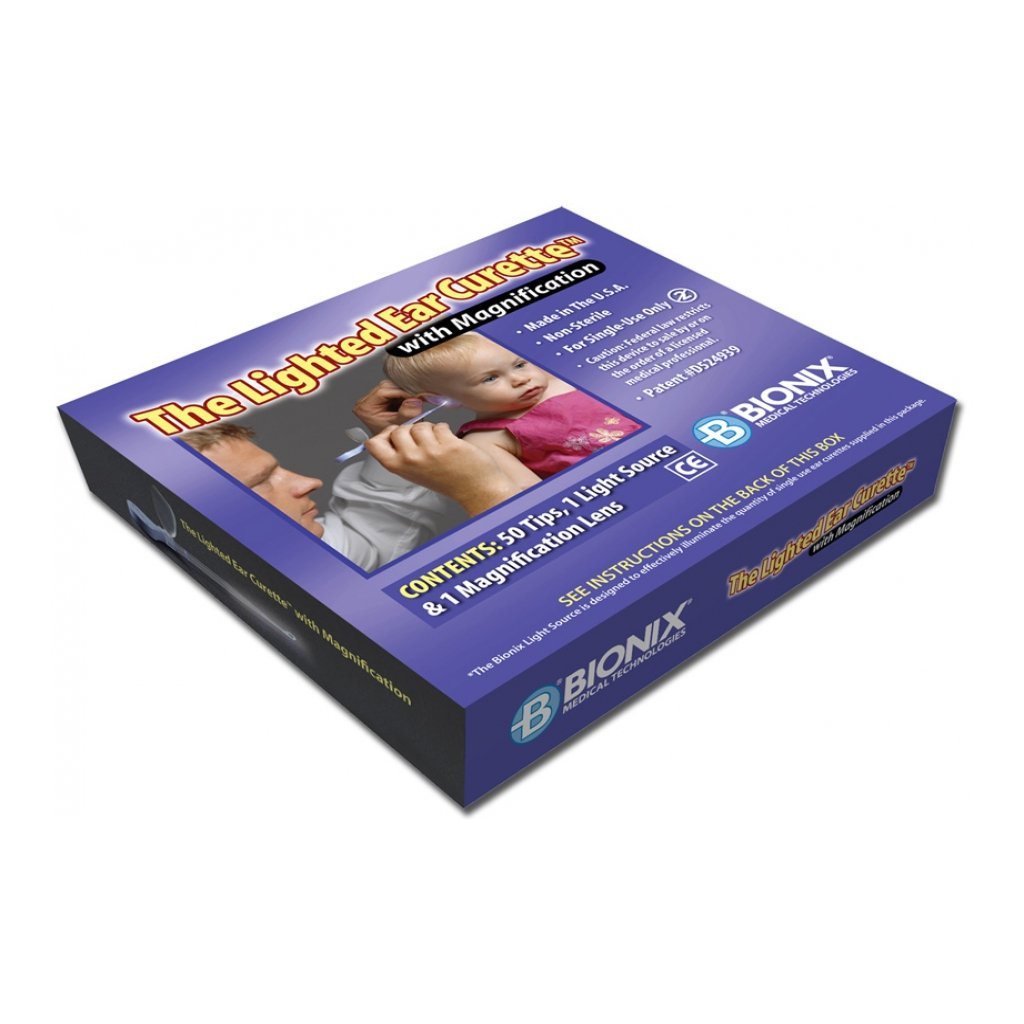

Flex Loop - Trasparente + 1 Illuminatore Led - Conf. 50 Pz.

Kit curette modello FLEXLOOP autoilluminanti.

Curette FLEXLOOP: Ansa da 4 mm per procedure di pulizia normali, molto flessibile e poco traumatica.

Il kit è composto da:

• 50 curette

• Un illuminatore a LED

• Lente